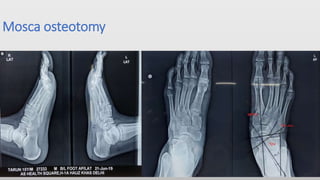

Mosca osteotomy

• Usually done after the age of 12